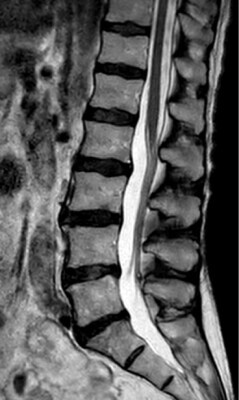

Al proporcionar una mayor resolución1, SmartSpeed de Philips ofrece una alta calidad de imagen para que los radiólogos puedan sentirse seguros a la hora de proporcionar información al médico especialista.

T2w TSE

Ingenia Ambition 1.5T